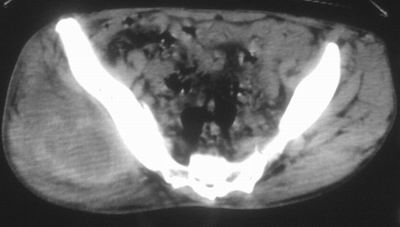

患者,男,63岁,自诉3个月前发现右臀部包块,触及疼痛,治疗后缩小。前天突然增大。无高热病史。

考虑-----右臀大肌,臀中肌---感染性病变可能性大。

病灶内部可见出血,首先考虑急性出血性病变.血肿?

给个骨窗,判断一下肿块是否与髂骨有关,肿块内出血是肯定的,至于是感染形成的脓肿还是起源于肌肉或纤维组织的肉瘤则难以确定,不过从影像上看,包膜完整,且环形增厚,病灶下部见斑片状底密度坏死,个人倾向感染可能性大

肌间隙明显混浊,三个月前治疗有缩小,支持考虑臀大肌下脓肿伴出血,肿瘤如果出现瘤内出血的话瘤外边界应该较清楚,现在表现为一种恶性征像,但骨质无明显异常,且臀小肌边界清楚,不符合恶性表现.